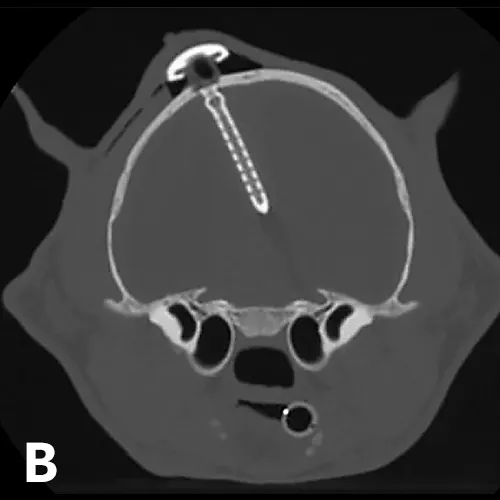

X-ray and CT images of a cat showing radiopaque ventriculoperitoneal shunt in place within skull.

FIGURE 5

(A) Postoperative lateral radiograph and (B) transverse CT image showing a ventriculoperitoneal shunt placed in a cat. Although the well was not flush with the skull, the shunt appeared stable after the sutures were tightened. The cat did well after surgery. Images courtesy of Dr. Eric Glass, Red Bank Veterinary Hospital/Compassion First Pet Hospitals

Surgical placement of a shunt is preferred, especially when medical management fails.1,2,11,12 Because return to normal condition is uncommon following surgery, the goal of shunt placement is improvement in clinical signs. Most commonly used is a ventriculoperitoneal shunt (Figure 5), which diverts CSF from the ventricular system through a tube tunneled through the subcutaneous tissues to the abdomen, where CSF is then reabsorbed.1,2 Patients with mild-to-moderate hydrocephalus often do well postoperatively; patients with severe hydrocephalus and only a thin rim of brain parenchyma are at higher risk for postoperative complications.1,2,9 If too much CSF is removed (ie, overshunting), the brain parenchyma may collapse, resulting in tearing of meningeal vessels and hemorrhage.1,2 Other postoperative complications can include undershunting; shunt infection or obstruction, which may necessitate replacement; and/or seizures.1,2